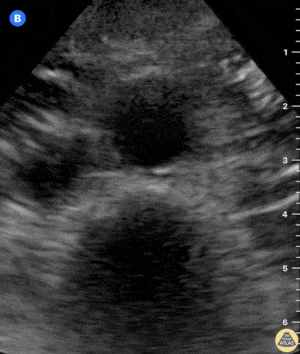

VCI: Kardiyak Tamponad Örnekleri

Tamponad ile Birlikte Sirkumferansiyel Perikardiyal Efüzyon

Kardiyak Tamponad